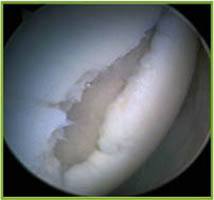

Graduação da Condromalácia:

■ I – amolecimento da cartilagem

■ II – fragmentação de cartilagem ou fissuras (diâmetro < 1,3cm)

■ III – fragmentação ou fissuras (diâmetro > 1,3cm)

■ IV – erosão ou perda completa da cartilagem articular